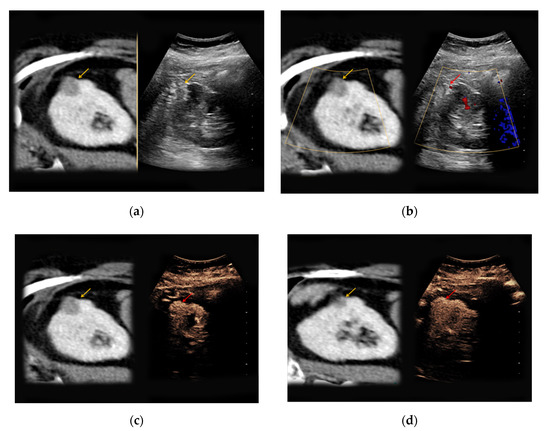

Figure 1. Renal oncocytoma in the right kidney with a diameter of 1.2 cm. (a) In native B-mode, the lesion presents as slightly hyperechoic (yellow arrow); (b) the lesion shows discrete vascularization in Doppler mode. (c) Upon intravenous application of SonoVue®, the lesion shows no signs of hyperenhancement.

Supplementary Table S1 illustrates the varying sonomorphological characteristics of renal oncocytomas and angiomyolipomas. No significant statistical differences between the sonomorphological features of benign vs. malignant lesions could be detected (Table 1). In native B-mode, oncocytomas presented as hypoechoic in seven cases (64%), as hyperechoic in one case (9%), and as isoechoic in one case (9%). Two lesions could not be detected in native B-mode and Doppler mode but demarcated upon intravenous application of SonoVue® showing rapid contrast-enhancement (18%). Only three lesions showed slight hypervascularization in Doppler mode (27%). In all patients with histopathologically confirmed oncocytoma, early contrast-enhancement upon application of SonoVue® could be detected (100%) (Figure 1). Seven of those lesions also showed venous wash-out (64%).